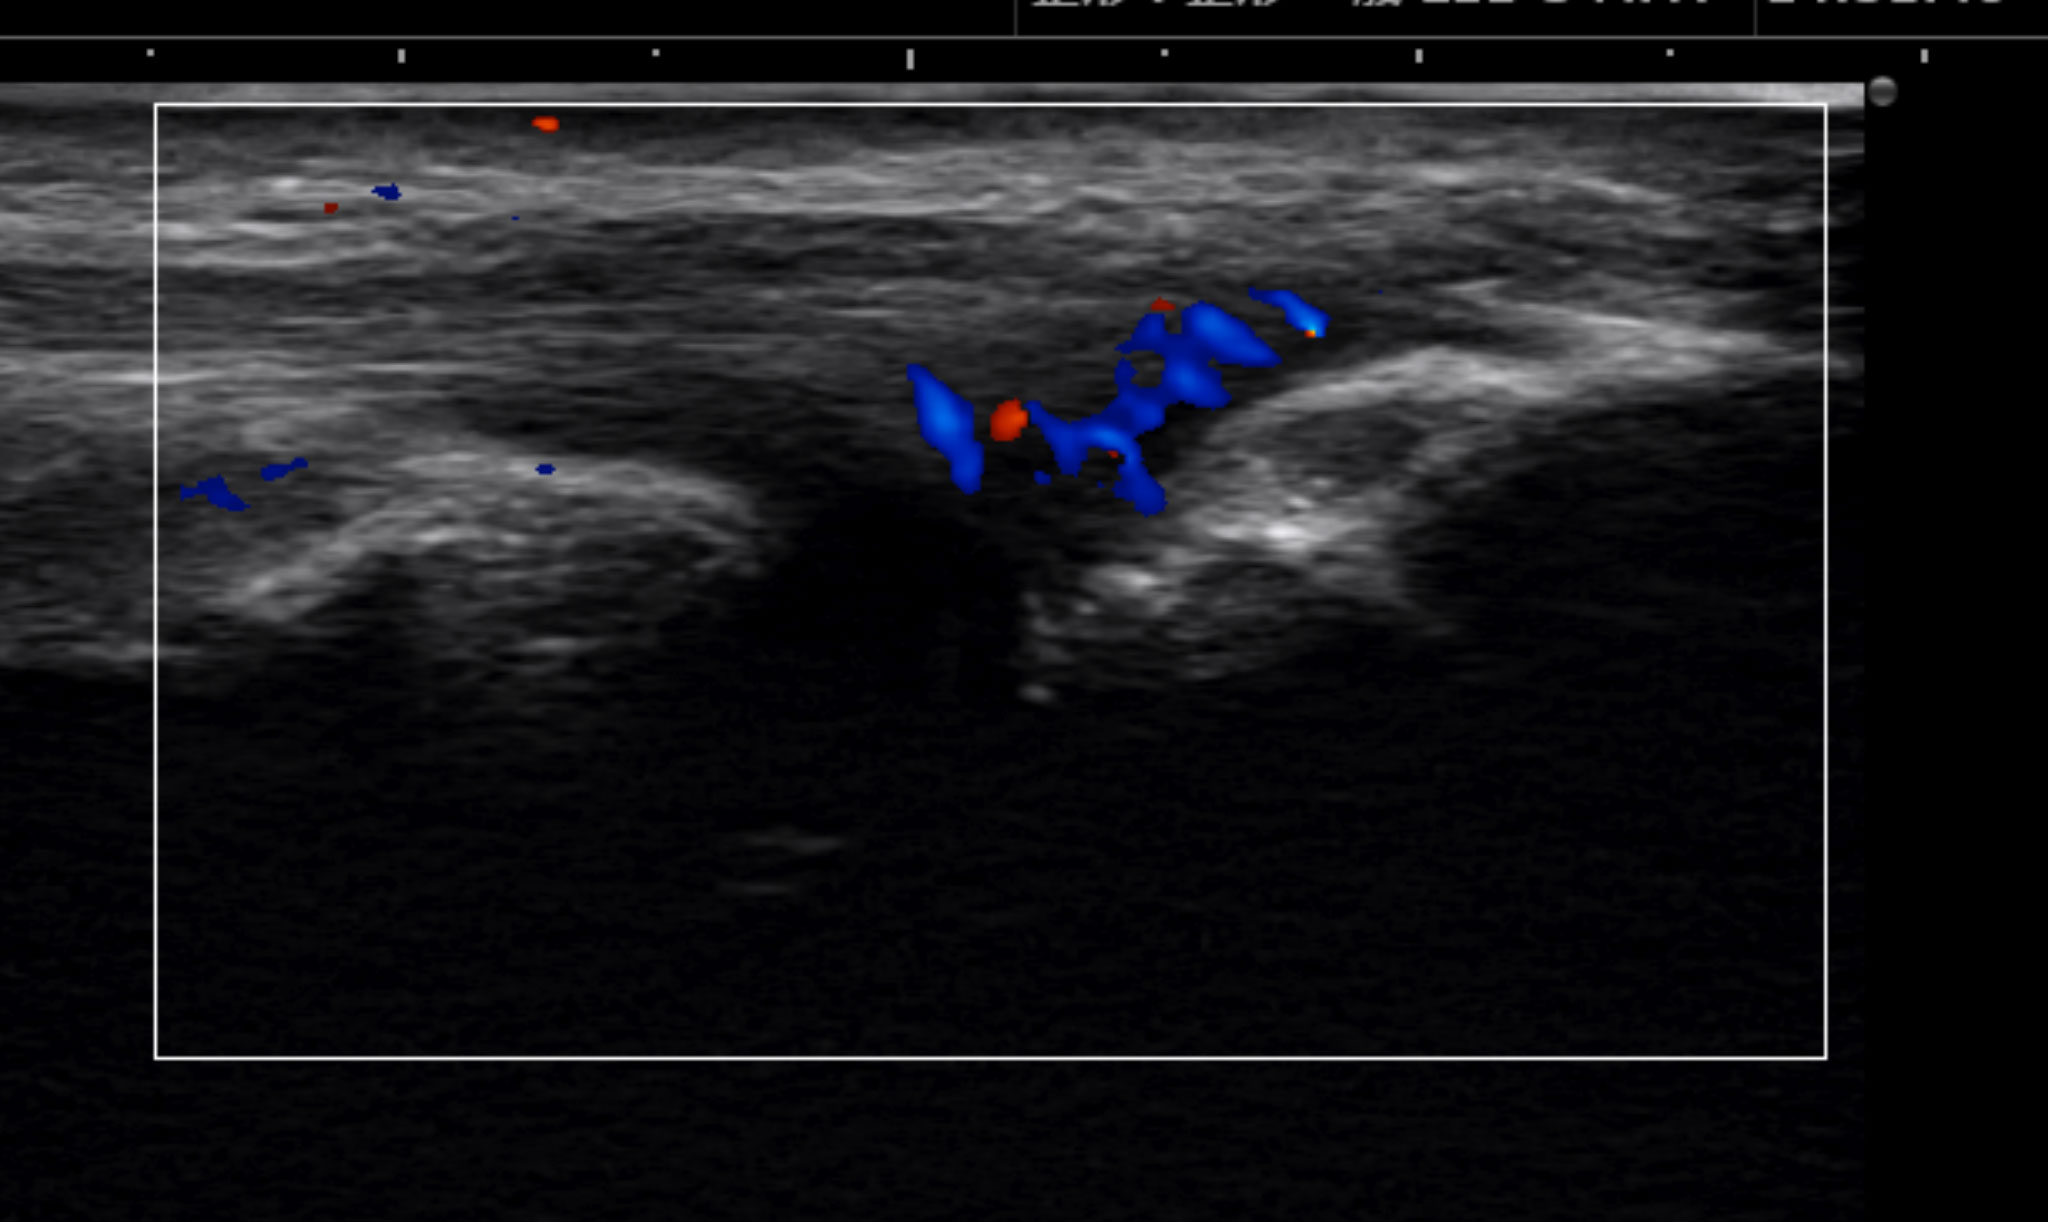

If conditions other than golfer’s elbow are suspected, the following examinations may be performed for differential diagnosis. Among these, magnetic resonance imaging (MRI) and ultrasonography (ultrasound examination) are considered the most effective.

Ultrasound image: the red and blue areas indicate the site of pain.

In medial epicondylitis, which is the underlying cause of golfer’s elbow pain, abnormal blood vessels may proliferate. Nerves often grow alongside these abnormal vessels, contributing to persistent pain. In recent years, a new outpatient treatment known as catheter-based therapy has been developed to reduce these abnormal blood vessels. This approach directly targets the abnormal neovascularization that is responsible for prolonged pain.